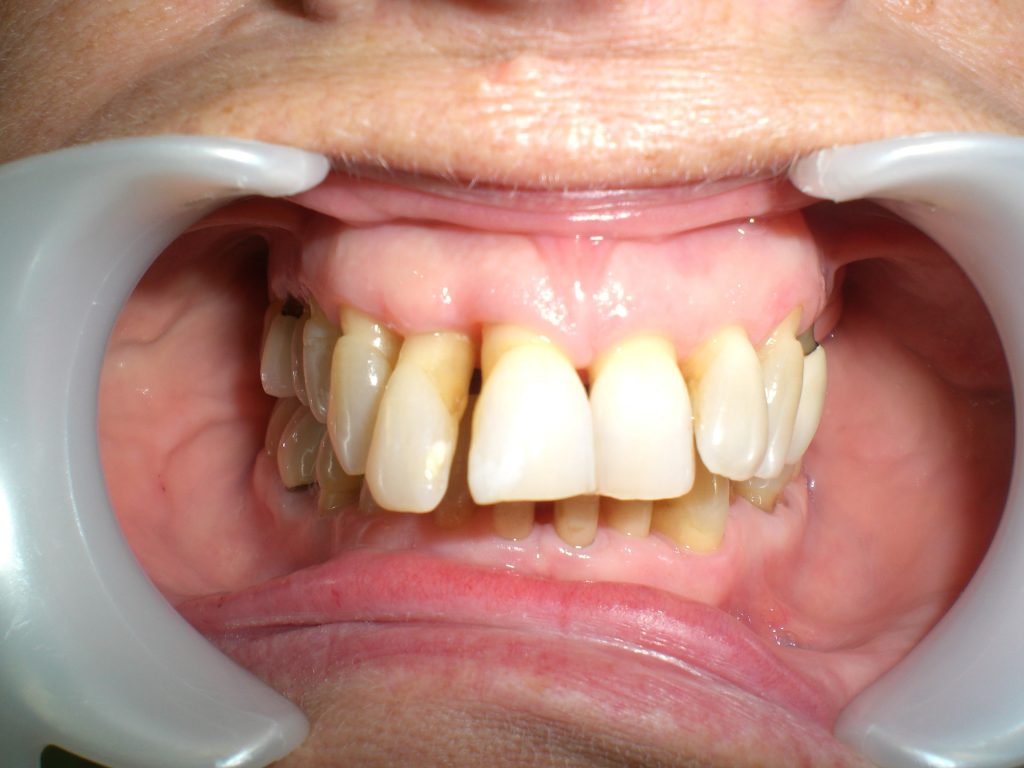

Arcade maxillaire avant traitement orthodontique, séquelles de maladie parodontale

Après traitement orthodontique et réalisation d’une attelle coulée collée (courtoisie Dr Patrick Fournier)